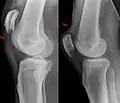

| An x-ray demonstrating quadriceps tendon rupture. Note the abnormal angle of the patella and soft-tissue swelling marked by the arrow. | |